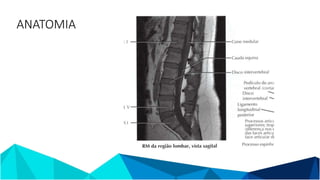

ANATOMIA